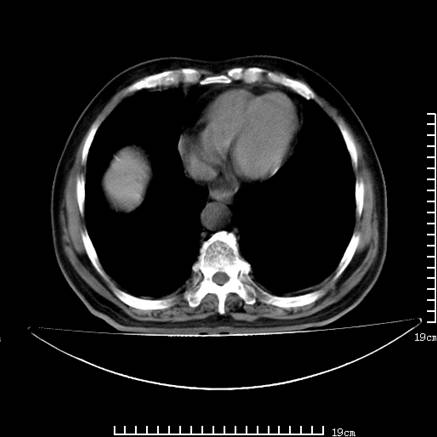

以下是引用zsl6918在2008-7-19 21:53:00的发言:[br]胆总管结石并胆系感染,胆囊切除术后改变。

以下是引用sch2008在2008-7-19 22:03:00的发言:[br]肝内胆管及胆总管积气,并胆总管结石,考虑;胆囊切除术后,胆系感染

以下是引用xinliheng001在2008-7-19 21:59:00的发言:[br]胰头段胆管结石肝内外胆管扩张积气。

以下是引用liaoqiang在2008-7-19 22:26:00的发言:[br]胆总管结石伴胆系感染。